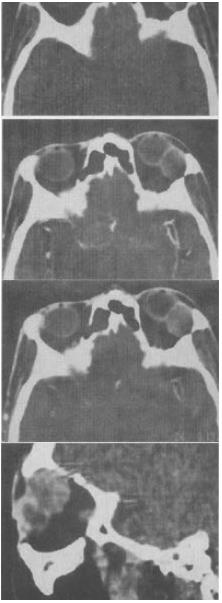

- 单项选择题 女,36岁,左眼眶外上部可触及一无痛性包块有2年,眼球向内下方突出,CT检查如图,最可能的诊断是()。

A、泪腺良性混合瘤

B、泪腺恶性上皮性肿瘤

C、炎性假瘤

D、淋巴瘤

E、淋巴瘤样增生

- A